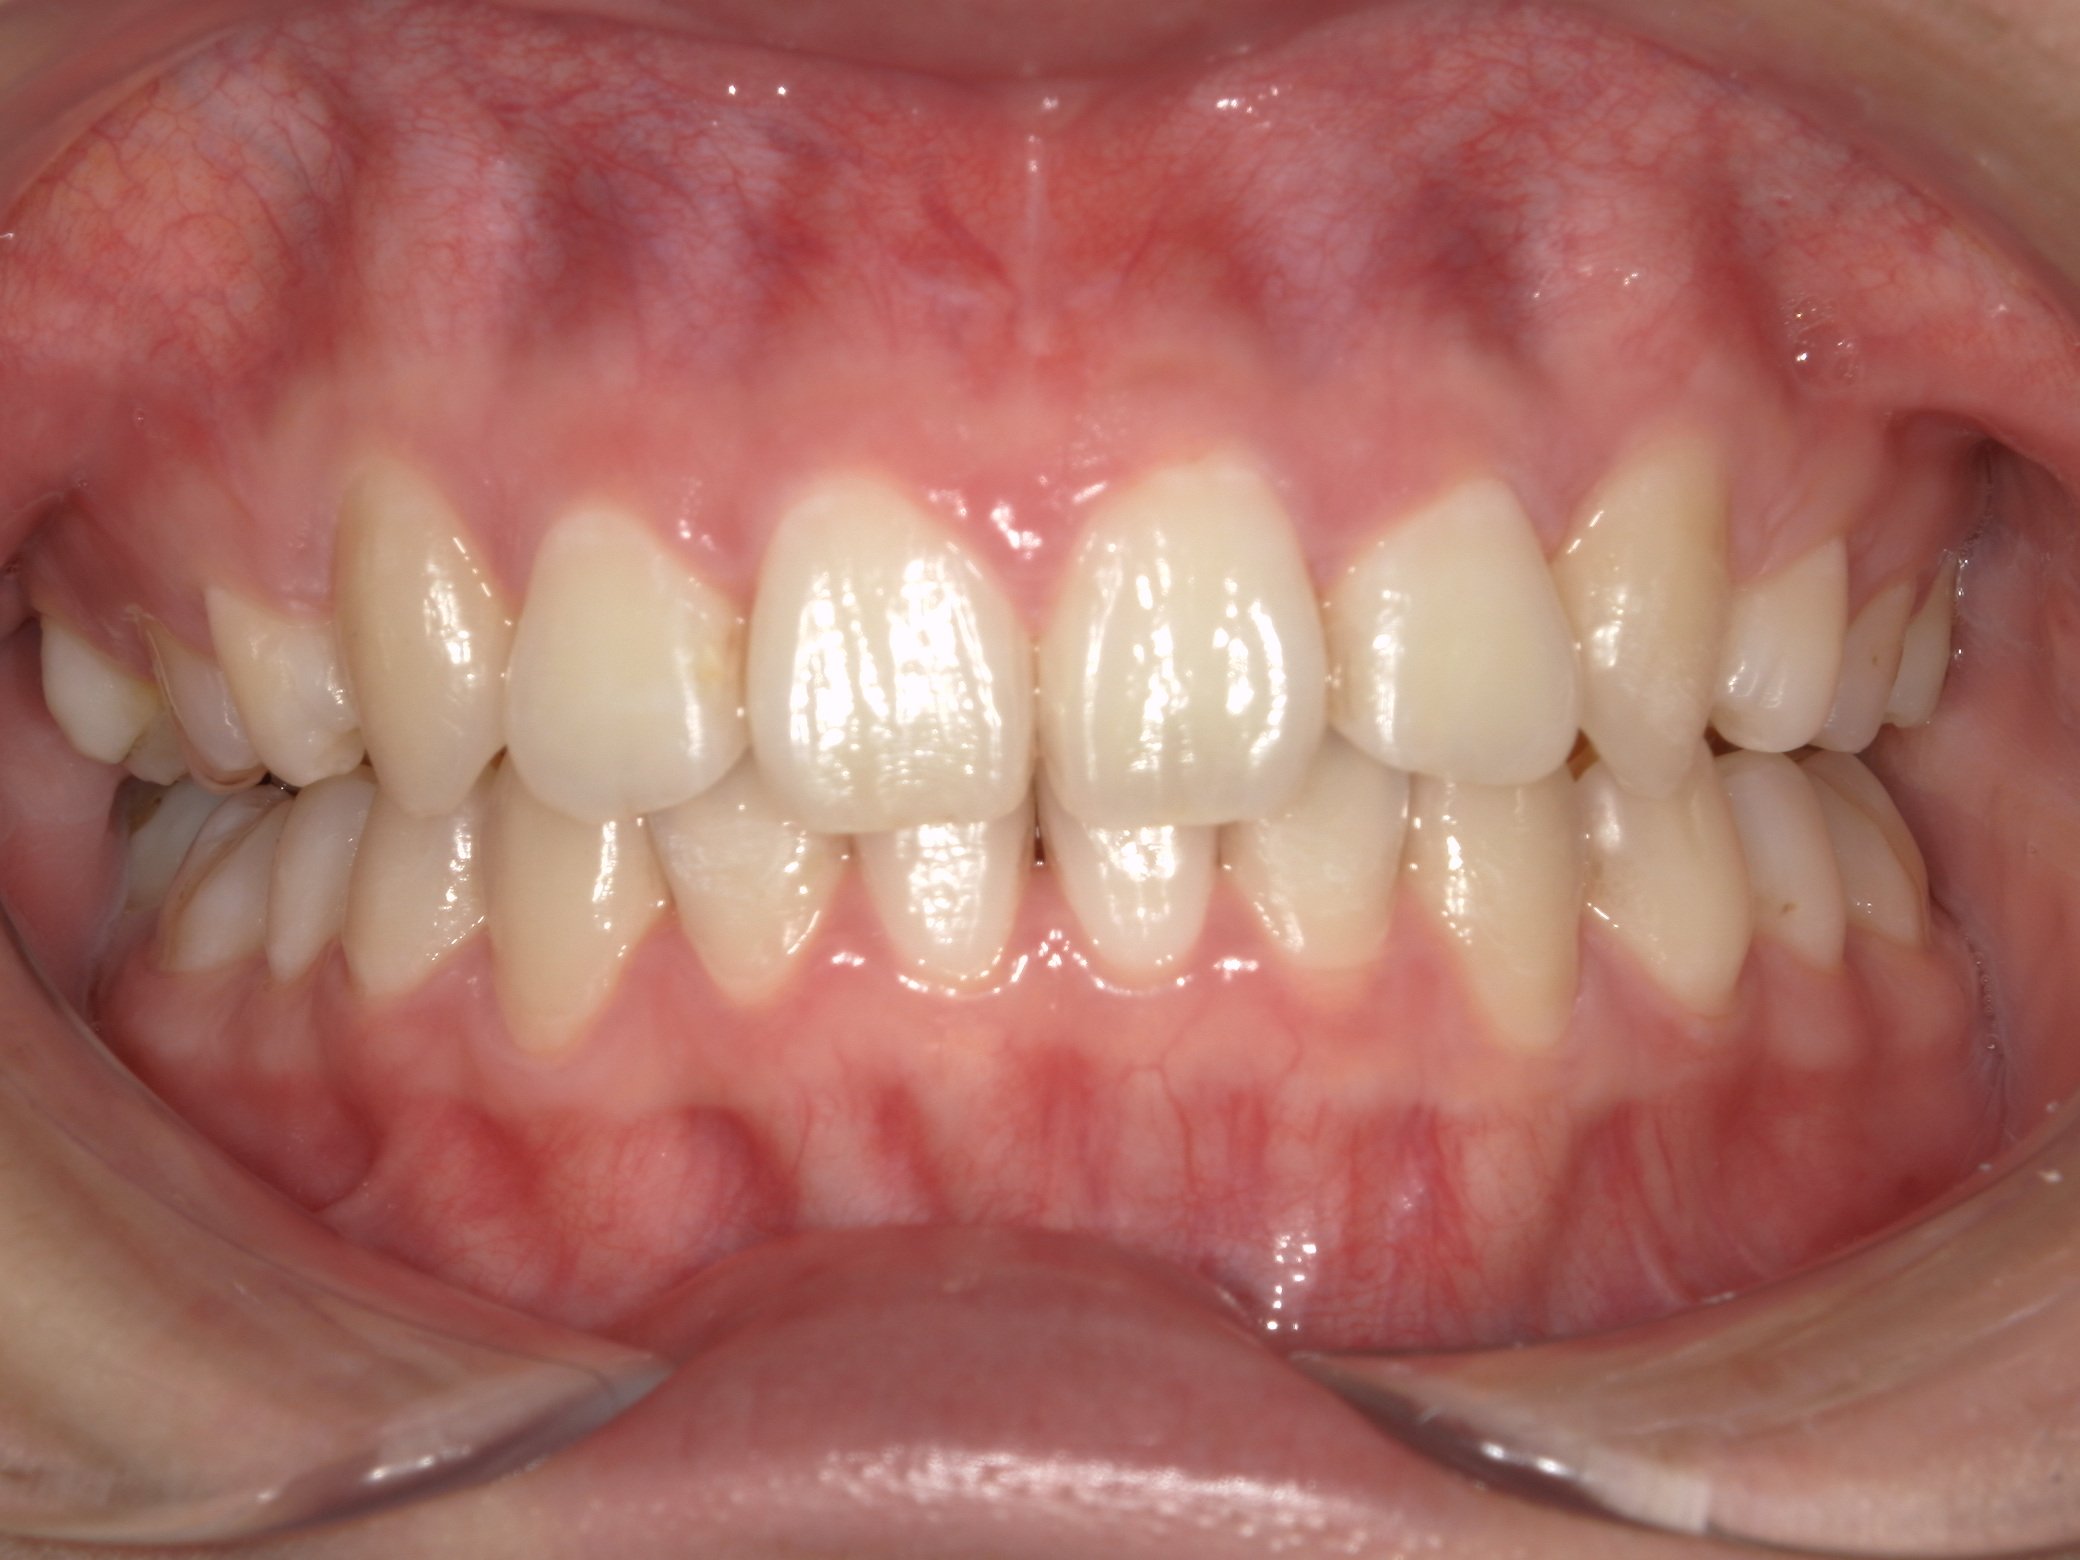

Before

(治療前)

患者様情報 19歳 男性 診断名 叢生 治療内容 マウスピース矯正(クリアコレクト) 期間・通院回数 20か月 / 9回 費用(総額) 755,000円(税込) リスク・副作用 治療の初期段階では痛みや不快感が生じやすくなりますが、通常1週間前後で慣れていきます。 当院で行うマウスピース矯正の特徴